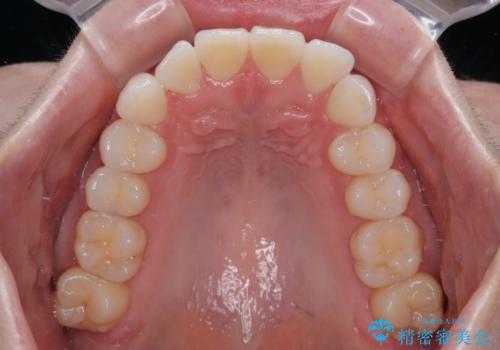

- 上下前歯の叢生を気にして来院された患者様です。

軽度な叢生であり、安価で短期間の治療を規模されていたため、インビザライン・モデレートを用いて矯正治療を行うこととしました。